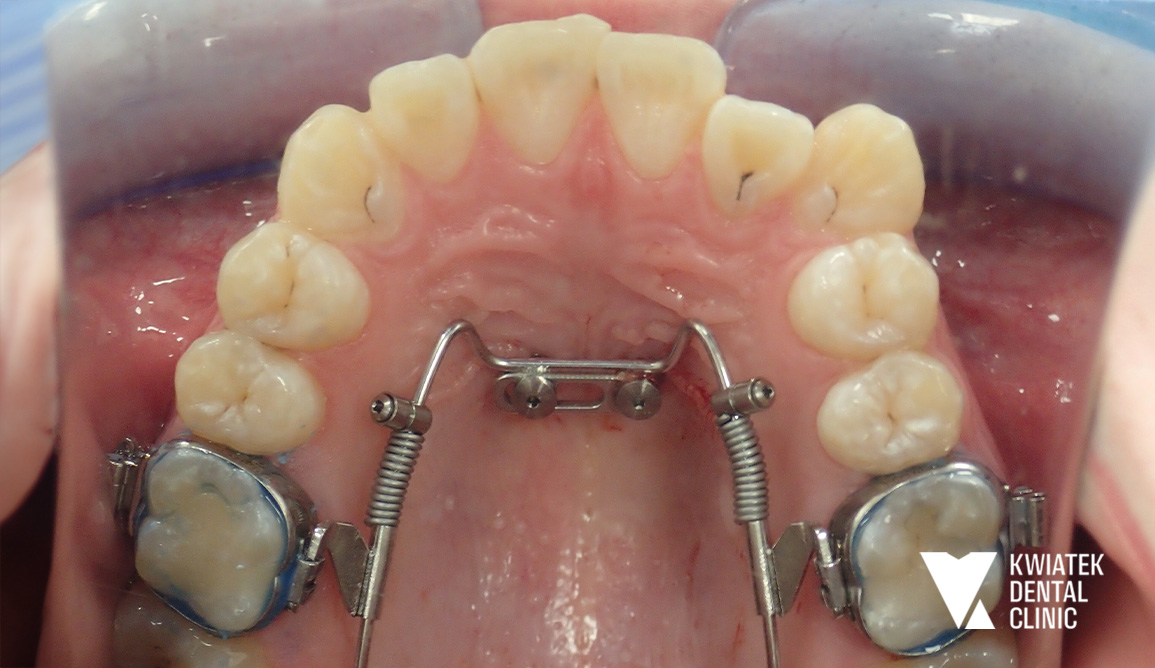

3. zastosowanie systemu ortodontycznego Beneslider opartego na miniimplantach podniebiennych

Leczenie rozpoczęto od profesjonalnej higienizacji jamy ustnej. Podczas wizyty stwierdzono znaczne nagromadzenie płytki bakteryjnej oraz kamienia nazębnego w przestrzeniach międzyzębowych, dlatego przeprowadzono dokładny instruktaż higieny oraz zalecono odpowiednie preparaty remineralizujące. Następnie wykonano chirurgiczne usunięcie zębów mądrości. Kluczowym etapem terapii było zastosowanie systemu Beneslider. Na podniebieniu wprowadzono dwa miniimplanty ortodontyczne o wymiarach 2.0/11 mm w znieczuleniu nasiękowym. Na zębach 16 i 26 osadzono pierścienie, a następnie zamontowano aparat dystalizujący umożliwiający przesunięcie zębów trzonowych do tyłu i uzyskanie przestrzeni w łuku. Po uzyskaniu odpowiednich warunków przestrzennych rozpoczęto leczenie aparatem stałym cienkołukowym zamkami samoligaturującymi. Aparat założono w obu łukach zębowych, a Pacjent otrzymał szczegółowy instruktaż higieny oraz zestaw ortodontyczny do codziennej pielęgnacji. W kolejnych miesiącach regularnie wykonywano wizyty kontrolne, podczas których aktywowano aparat, stosowano łuki ortodontyczne o różnej sztywności oraz elementy dodatkowe. W trakcie leczenia przeprowadzono także leczenie zachowawcze z użyciem materiałów kompozytowych w koferdamie i pod kontrolą mikroskopu. Równolegle wykonywano okresowe higienizacje oraz kontrolowano stan jamy ustnej, aby utrzymać zdrowe środowisko podczas terapii ortodontycznej.